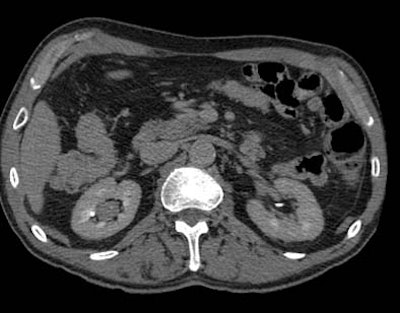

| Postprocessing or reformatting images may obscure the diagnosis. TCC clearly seen on axial CT (above) and on coronal multiplanar reformat below. But even a thin-slab MIP reformat masks detection of the right-upper-pole TCC (bottom). Images courtesy of Dr. Nigel Cowan. |